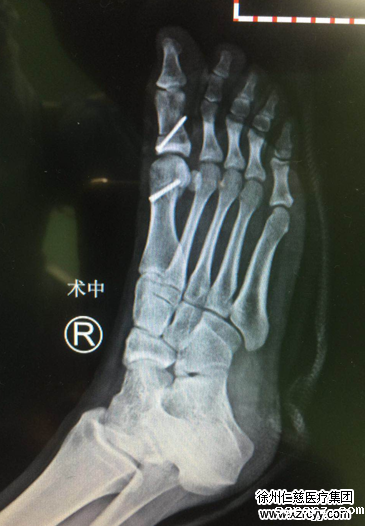

经过检查,小旭的右足踇指自跖趾关节向外侧偏斜移位,踇外翻角约37°,跖间角约15°,第一跖骨头内侧膨大,踇囊形成。采取Chevron+akin截骨进行踇外翻矫正手术,于是对小旭安排了住院准备手术。

苏省医生配合曹主任对小旭的踇外翻进行了手术,术中切除跖骨头骨赘,对第一跖骨远端和近节跖骨做截骨。术后不久,小旭就可以下床行走,疼痛消失。

术中